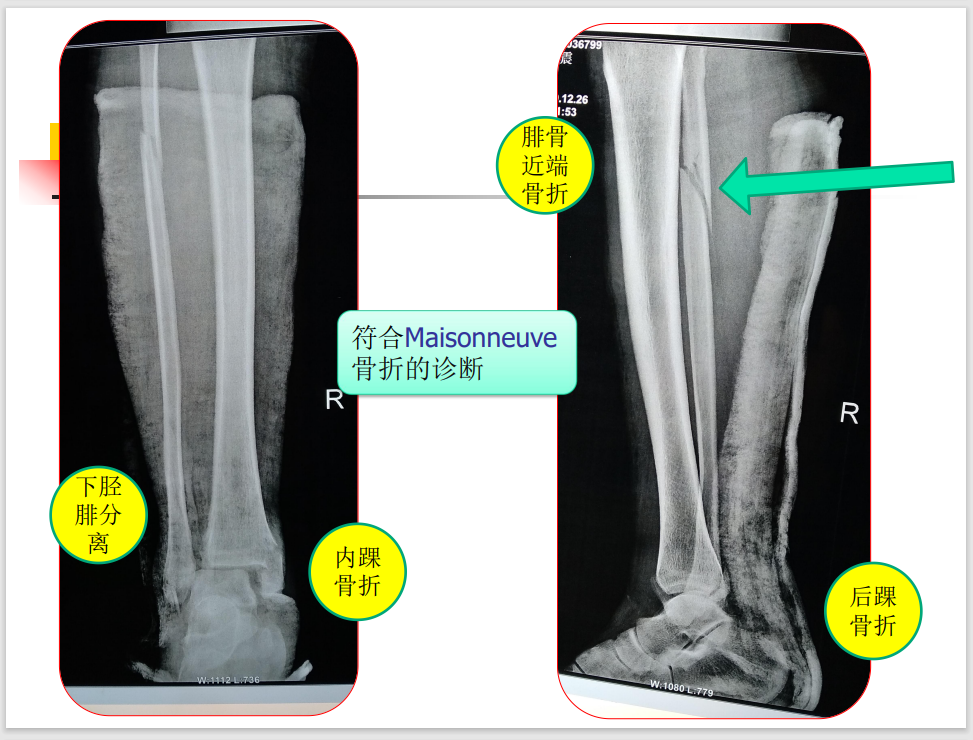

特殊类型踝关节骨折虽然临床少见,但是其诊断、治疗不准确会带来诸多不良后遗症,以致踝关节功能障碍,今天我们就来学习一下Maisonneuve 骨折!